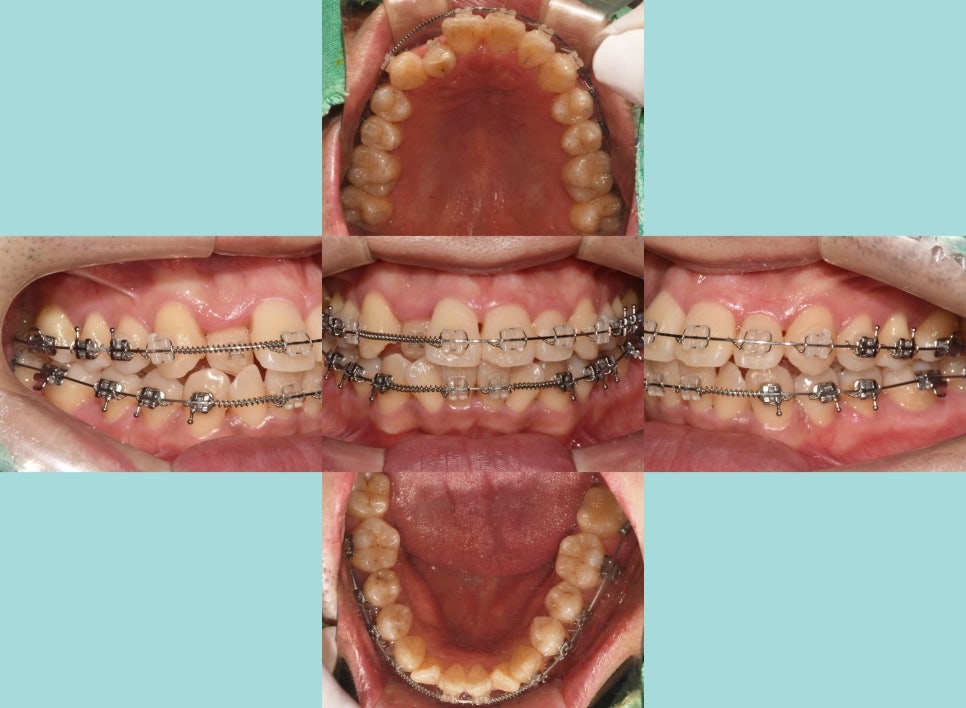

최종 완료된 모습에서는

전과 달리 가지런해진 배열로

많이 깔끔해진 느낌이 드는데요.

반대로 물리고 있었던 12번도

이제는 전방으로 이동이 잘 되어

현재는 윗니가 아랫니를 피개하는 형태로

잘 유지를 하고 있습니다.

앞니 뻐드렁니로 돌출되어 나왔던 부분도

후방 견인 과정을 통해

자연스러운 아치를 가질 수 있도록

마무리하면 모든 과정은 끝납니다.

전반적인 총생 치료로 인해

구강 내 많은 좋은 변화들이 일어나

인상 또한 밝고 깔끔해진 느낌을 받습니다.

치료 기간: 22.12~24.09